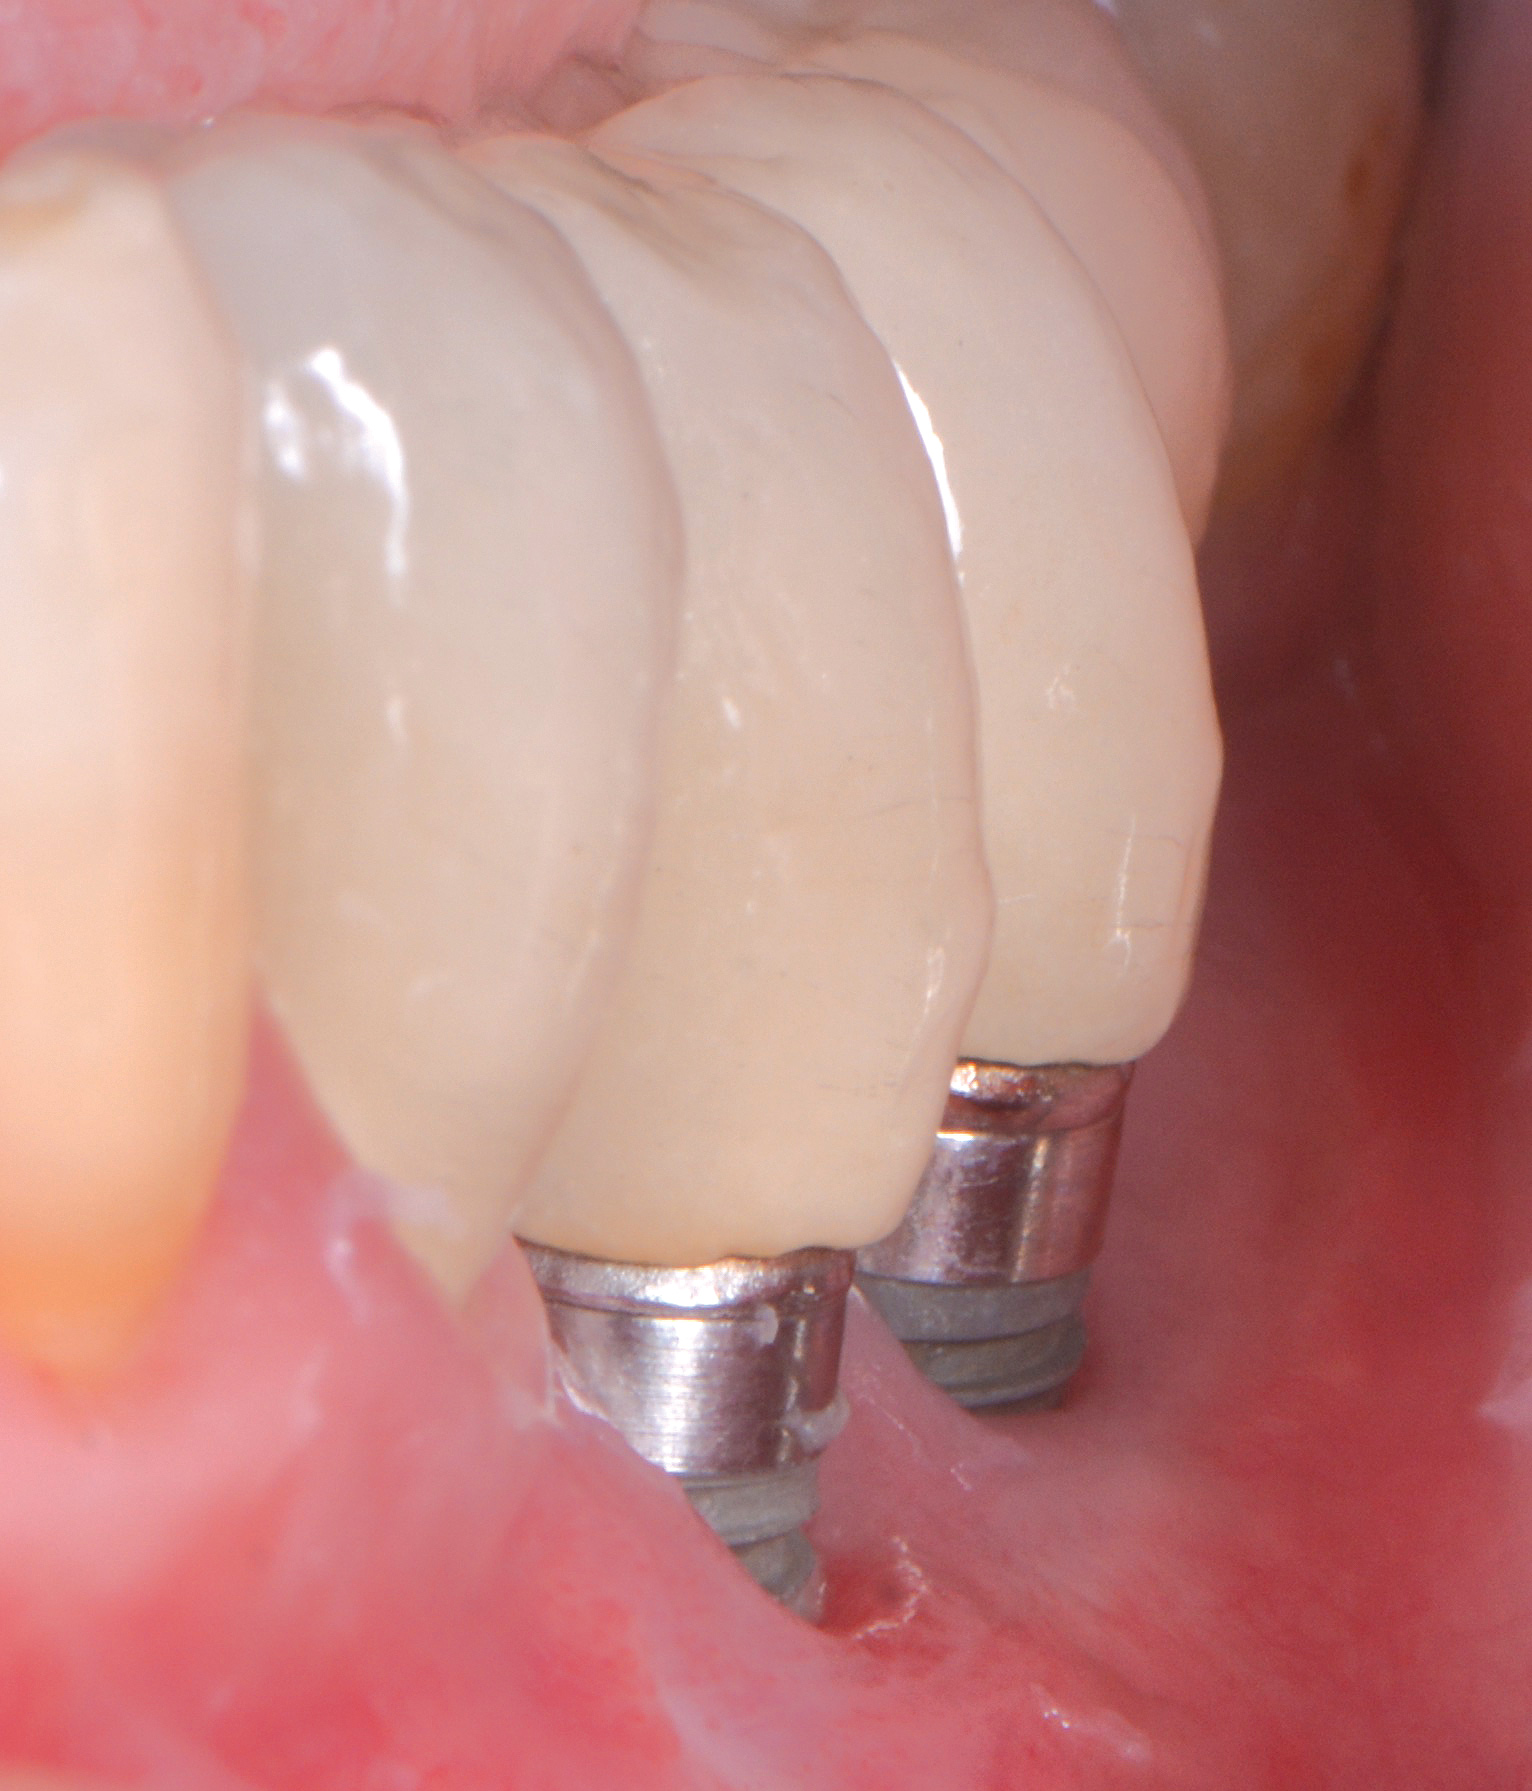

Dental implants have revolutionized the way in which clinicians treat and restore partially and fully edentulous patients and have demonstrated success for managing a broad range of clinical dilemmas. While implants have been highly predictable and have achieved long-term success, they are not immune from complications associated with improper treatment planning, poor surgical and prosthetic execution, material failure, and inadequate or infrequent maintenance. Among these problems are the biologic complications of peri-implant mucositis and peri-implantitis, which are inflammatory conditions in the soft and/or hard tissues surrounding dental implants (Figure 1 through Figure 4).1,2